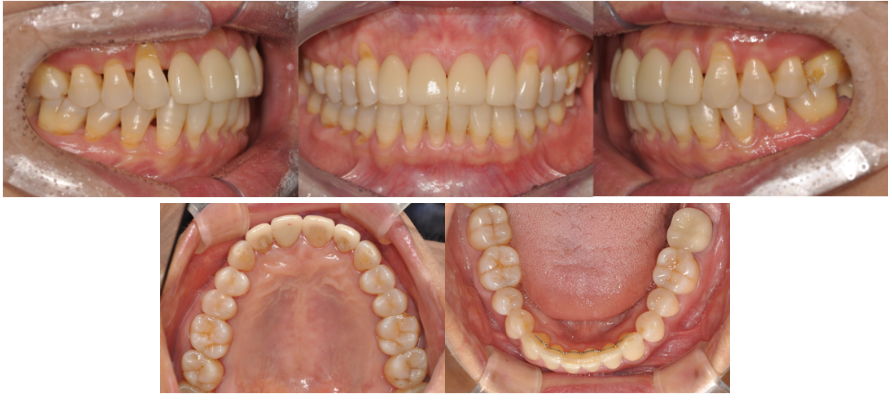

20대 여성

상악 앞니 사이 넓은 공간

아래턱이 약간 전방으로 나온 골격적 특징

왼쪽 아래 앞니가 앞으로 돌출

돌출된 아래 앞니와 맞닿는 윗니 끝 모서리가 이미 파절(깨짐)

보철만으로 앞니 공간을 채우려면

아래 앞니와 부딪히지 않도록 윗니를 더 앞으로 돌출되게 제작해야 하는 상황이었습니다.

아래 앞니 부분교정 진행

**치간삭제(IPR)**로 돌출된 앞니를 뒤로 정리

약 4개월간의 단기 교정치료로 보철 환경 최적화

앞니 공간을 과하게 채우지 않아도 되는 보철 환경 확보

윗니를 더 앞으로 내밀 필요가 없어 자연스러운 보철물 제작 가능

치아 크기·형태가 조화롭게 개선

교합 간섭 없이 안정적인 치아 접촉 형성